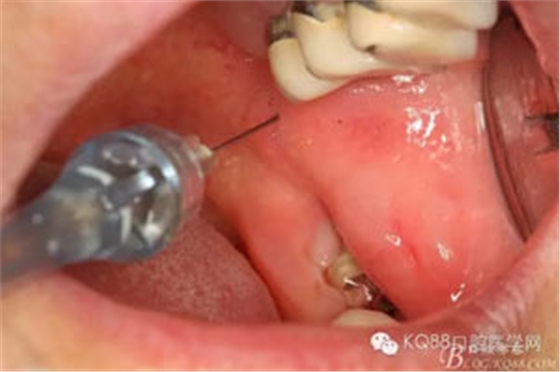

圖3. 采用局部無痛下牙槽神經(jīng)阻滯麻醉+38浸潤麻醉

圖4. 外加38局部浸潤麻醉、